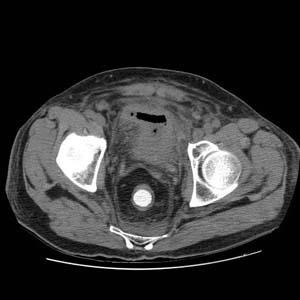

RADIOLOGY: GENITOURINARY: GU: Case# 32976: HYDRONEPHROSIS. URETEROVESICAL JUNCTION STONE. 58 year-old male with elevated creatinine.